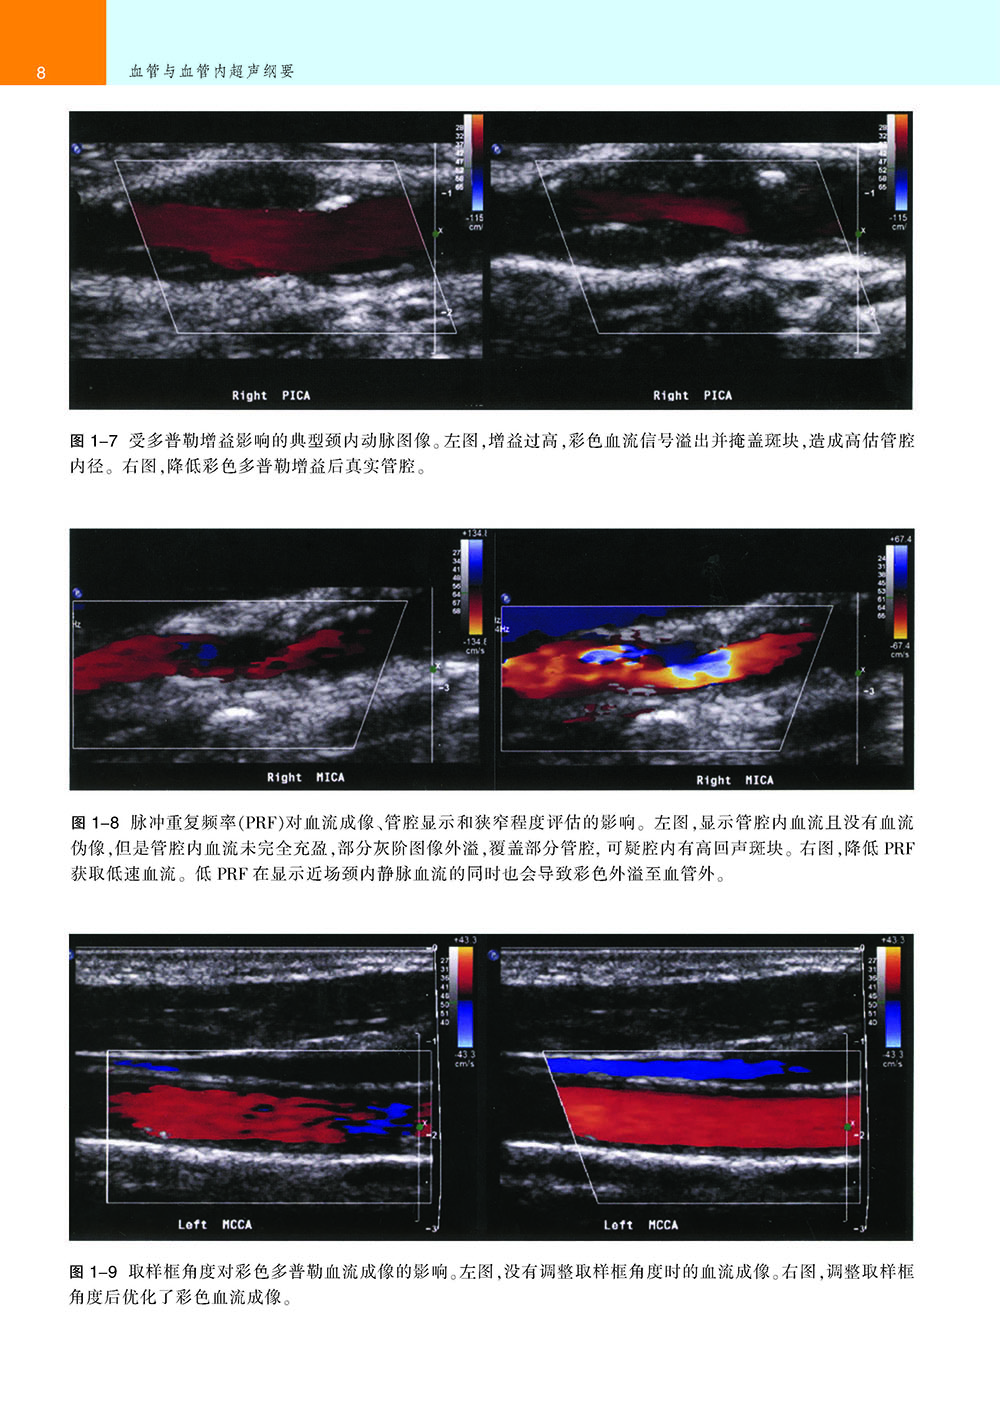

●血管及血管内超声图像及其详尽的注释。

●血管及血管内超声操作中如何获得高质量图片及避免伪影的指导。